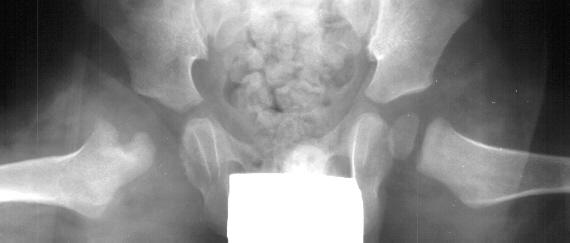

This case is an example of untreated septic arthritis which caused avascular

necrosis of the proximal femur. The primary cause of this is undrained

septic hip. Repeated aspiration is not adequect treatment of a septic hip.